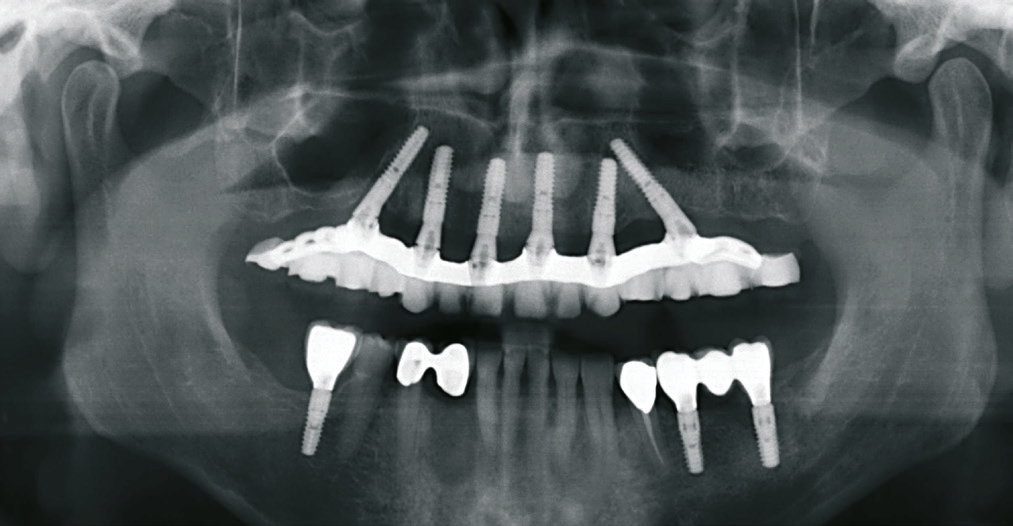

Zur implantatgetragenen prothetischen Versorgung zahnloser Patienten stehen dem Behandlungsteam verschiedene Konzepte zur Verfügung. Die Bemühungen nach möglichst einfachen Behandlungsmethoden führten in den vergangenen Jahren zur Modifikation klassischer Protokolle. So kann beispielsweise mit dem Konzept der Sofortversorgung die Behandlungszeit signifikant reduziert werden. Die Arbeitsgruppe um Prof. Dr. P. Maló hat das Konzept der schräg in den Kiefer inserierten Implantate zur festsitzenden Therapie des zahnlosen Ober- und Unterkiefers – unter Vermeidung von Sinusbodenelevation und Nervlateralisation – etabliert [3-5]. Die Untersuchungen der Arbeitsgruppe zeigen eine kumulative Überlebensrate von 97,6 Prozent [8]. Grundsätzlich erfordert das in seinem Aufwand reduzierte Therapiekonzept eine exakte präoperative Diagnostik sowie abgestimmte, für die Indikation konzipierte Implantatbauteile [1,6,7]. Ein seit Jahren bewährtes System basierend auf dem Protokoll ist SKY fast & fixed (bredent medical, Senden). Zusätzlich zur Möglichkeit der sofortigen temporären Versorgung liegen die Vorteile in der flexiblen Umsetzung der finalen Restauration. Aufgrund der hohen Patientenakzeptanz der temporären Brücke wird bis zur Herstellung der definitiven Versorgung ein großes Zeitfenster geboten, in welchem u. a. die Patientenbedürfnisse evaluiert werden können. In der Regel kann nach drei bis vier Monaten mit der Umsetzung der definitiven Versorgung begonnen werden [1].

Unter anderem beruht die Akzeptanz des Konzeptes darauf, den vorhandenen Knochen bestmöglich zu nutzen und knochenaufbauende Maßnahmen weitestgehend zu minimieren. Dadurch können sich jedoch unter Umständen ungünstige Implantataustrittstellen ergeben, was bei der Gestaltung der Suprakonstruktion limitierend ist, z.B. wenn der Schraubenkanal im sichtbaren Bereich platziert werden müsste. Um in diesen Situationen entsprechend Spielraum für die ästhetische Gestaltung zu schaffen, kann die transversale Verschraubung (Verbolzung) des Zahnersatzes mit den Implantaten eine adäquate Möglichkeit sein. Hierfür werden Prothetikkappen angeboten (bredent medical), die eine transversale Verschraubung – selbstzentrierende Transversalverschraubung – ermöglichen. Die Schraubenkanäle werden in den nicht sichtbaren Bereich positioniert. Die industriell vorgefertigten Bauteile vereinfachen die Arbeit und stellen eine hohe Präzision sicher. Das Vorgehen wird anhand eines Patientenfalles beschrieben. Es wird gezeigt, dass mit der transversalen Verschraubung selbst schwierige Ausgangsverhältnisse sicher und zuverlässig gelöst werden können.

Der Patient konsultierte während der kommenden Wochen regelmäßig die Praxis. Der postoperative Verlauf gestaltete sich problemlos. Nach vier Monaten zeigten sich osseointegrierte Implantate sowie stabile Hart- und Weichgewebeverhältnisse. Für die Herstellung der definitiven Brücke sind unterschiedliche Konzepte möglich. In diesem Fall sollte eine verschraubte Versorgung gefertigt, das Gerüst mit Komposit verblendet sowie die Restauration farblich individualisiert werden. Da schon bei der Herstellung der temporären Brücke festgestellt worden ist, dass die okklusale Verschraubung aufgrund der sichtbaren Schraubenkanäle zu ästhetischen Problemen führt, war eine transversale Verschraubung (Verbolzung) des Zahnersatzes auf den Implantaten angedacht.

Nach einer Überabformung wurde die provisorische Versorgung entnommen und die Situation abgeformt. Für die Evaluation der ästhetischen und funktionellen Parameter des Zahnersatzes war eine Ästhetikeinprobe indiziert. Das Set-up dafür wurde auf einer verschraubten Basis aus lichthärtendem Kunststoff angefertigt. Im Labor erfolgte die Herstellung des Gerüstes unter Berücksichtigung der transversalen Verschraubung. Die Verbindungselemente wurden in das Gerüst eingearbeitet. Grundsätzlich stellt die auf Implantaten verschraubte Restauration eine hohe Anforderung an die Gerüstpassung, da aufgrund der starren Verbindung der Implantate mit dem Knochen ein geringer Krafteinsatz eine hohe Auslenkung zur Folge haben kann. Eine Gerüsteinprobe im Mund bestätigte die spannungsfreie Passung. Es folgte die Verblendung des Gerüstes nach bekanntem Vorgehen. Mehrschichtige Verblendschalen aus einem High-Impact PMMA-Komposit (novo.lign, bredent) und lichthärtende Komposite unterstützten die einfache ästhetische Charakterisierung.

Das Aufschrauben der definitiven Brücke gestaltete sich problemlos. Nach Abnahme der temporären Versorgung ist die fertiggestellte Brücke über die Prothetikkappen bzw. die Verbolzungen auf den Implantaten befestigt worden (Abb. 5 und 6). Bei den posterioren Implantaten wurde der Schraubenzugang vom Zahntechniker nach vestibulär – außerhalb des sichtbaren Bereichs – gelegt (Abb. 7 und 8). Die anderen Implantate wurden im palatinalen Bereich verschraubt (Abb. 9). Aufgrund der Drei-Punkt-Fixierung ist ein Verkippen oder das Rotieren des Zahnersatzes ausgeschlossen. Da die Schraube in der Sekundärkonstruktion „gefangen“ ist, wird die Anwendung im Mund erleichtert. Ein lästiges Einfädeln entfällt. Bereits mit zwei bis drei Umdrehungen ist eine Schraube fixiert. Weder ästhetisch noch funktionell treten Beeinträchtigungen auf.